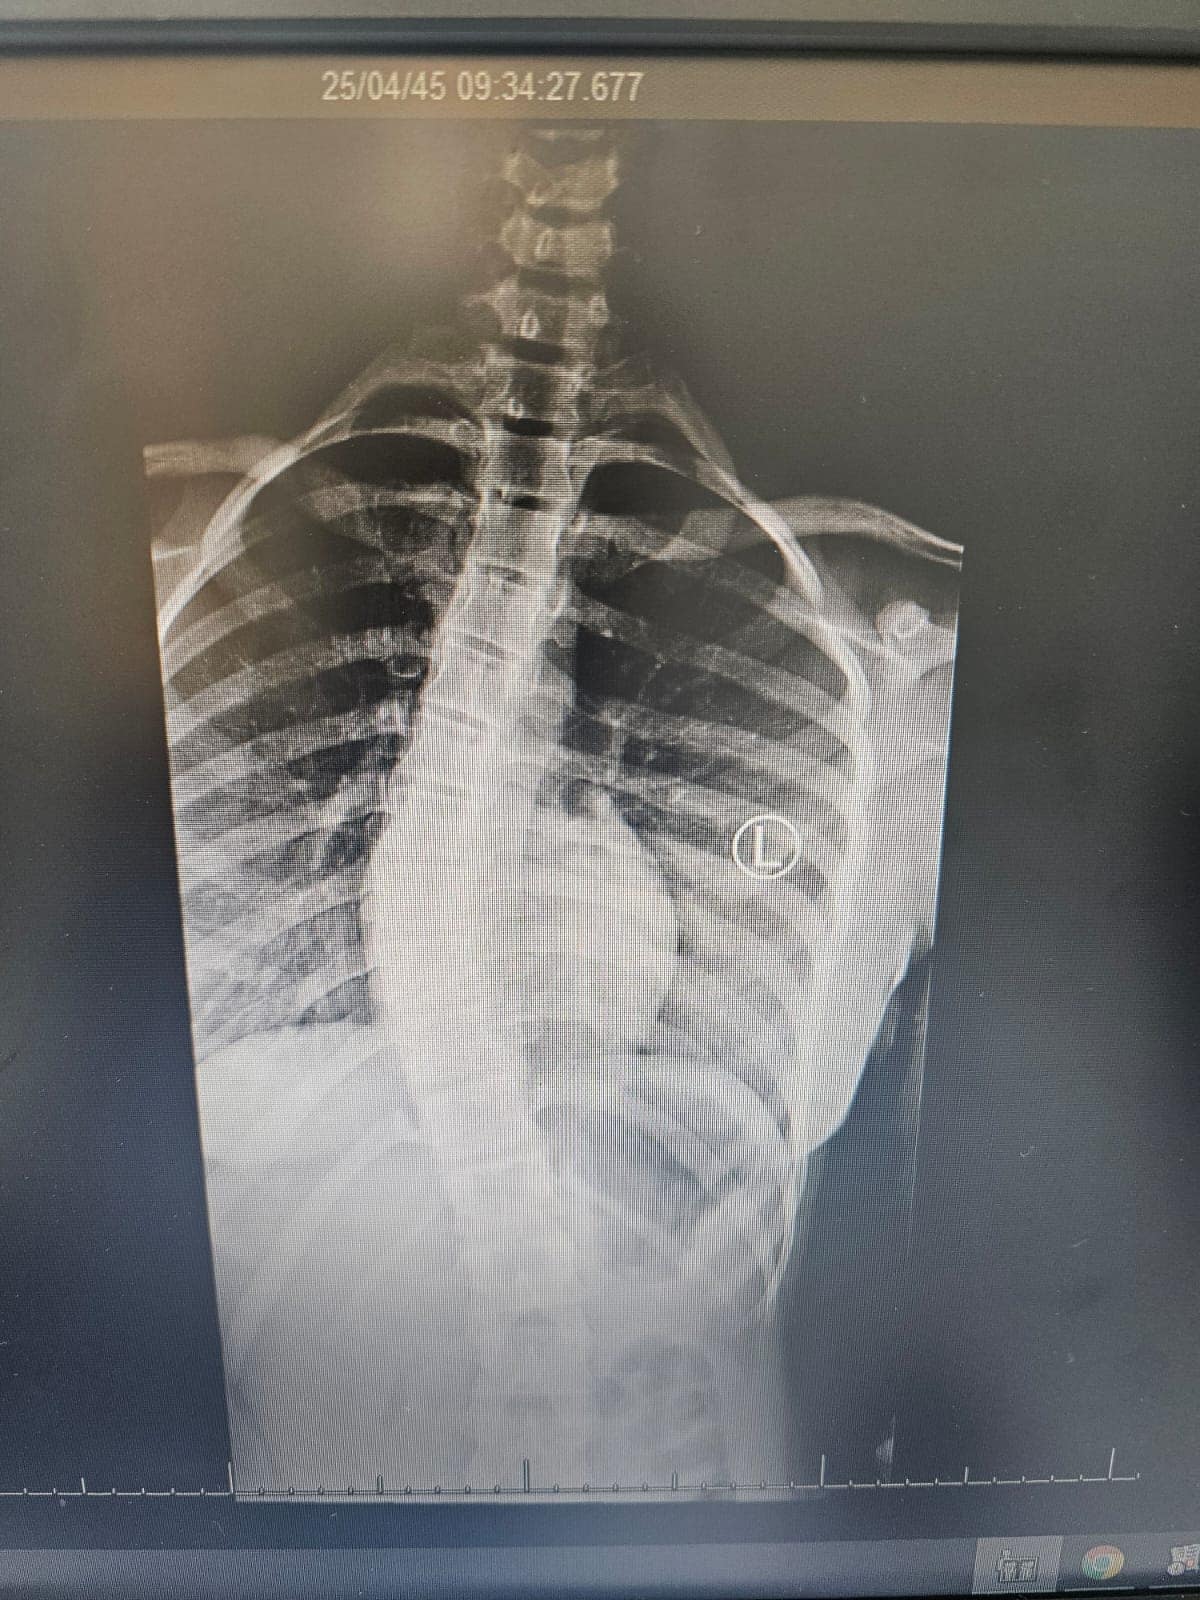

وأوضح تجمع عسير الصحي نطاق بيشة ، أن الطفله حضرت إلى المستشفى وبعد عمل الأشعة والتحاليل اللازمة شٌخصت الحالة على أنها جنف شديد مع وجود صعوبة في أداء وممارسة الأنشطة اليومية ومشكلات في النوم نتيجة إصابتها بانحرافٍ شديدٍ في العمود الفقري (الجنف) منذ الطفوله